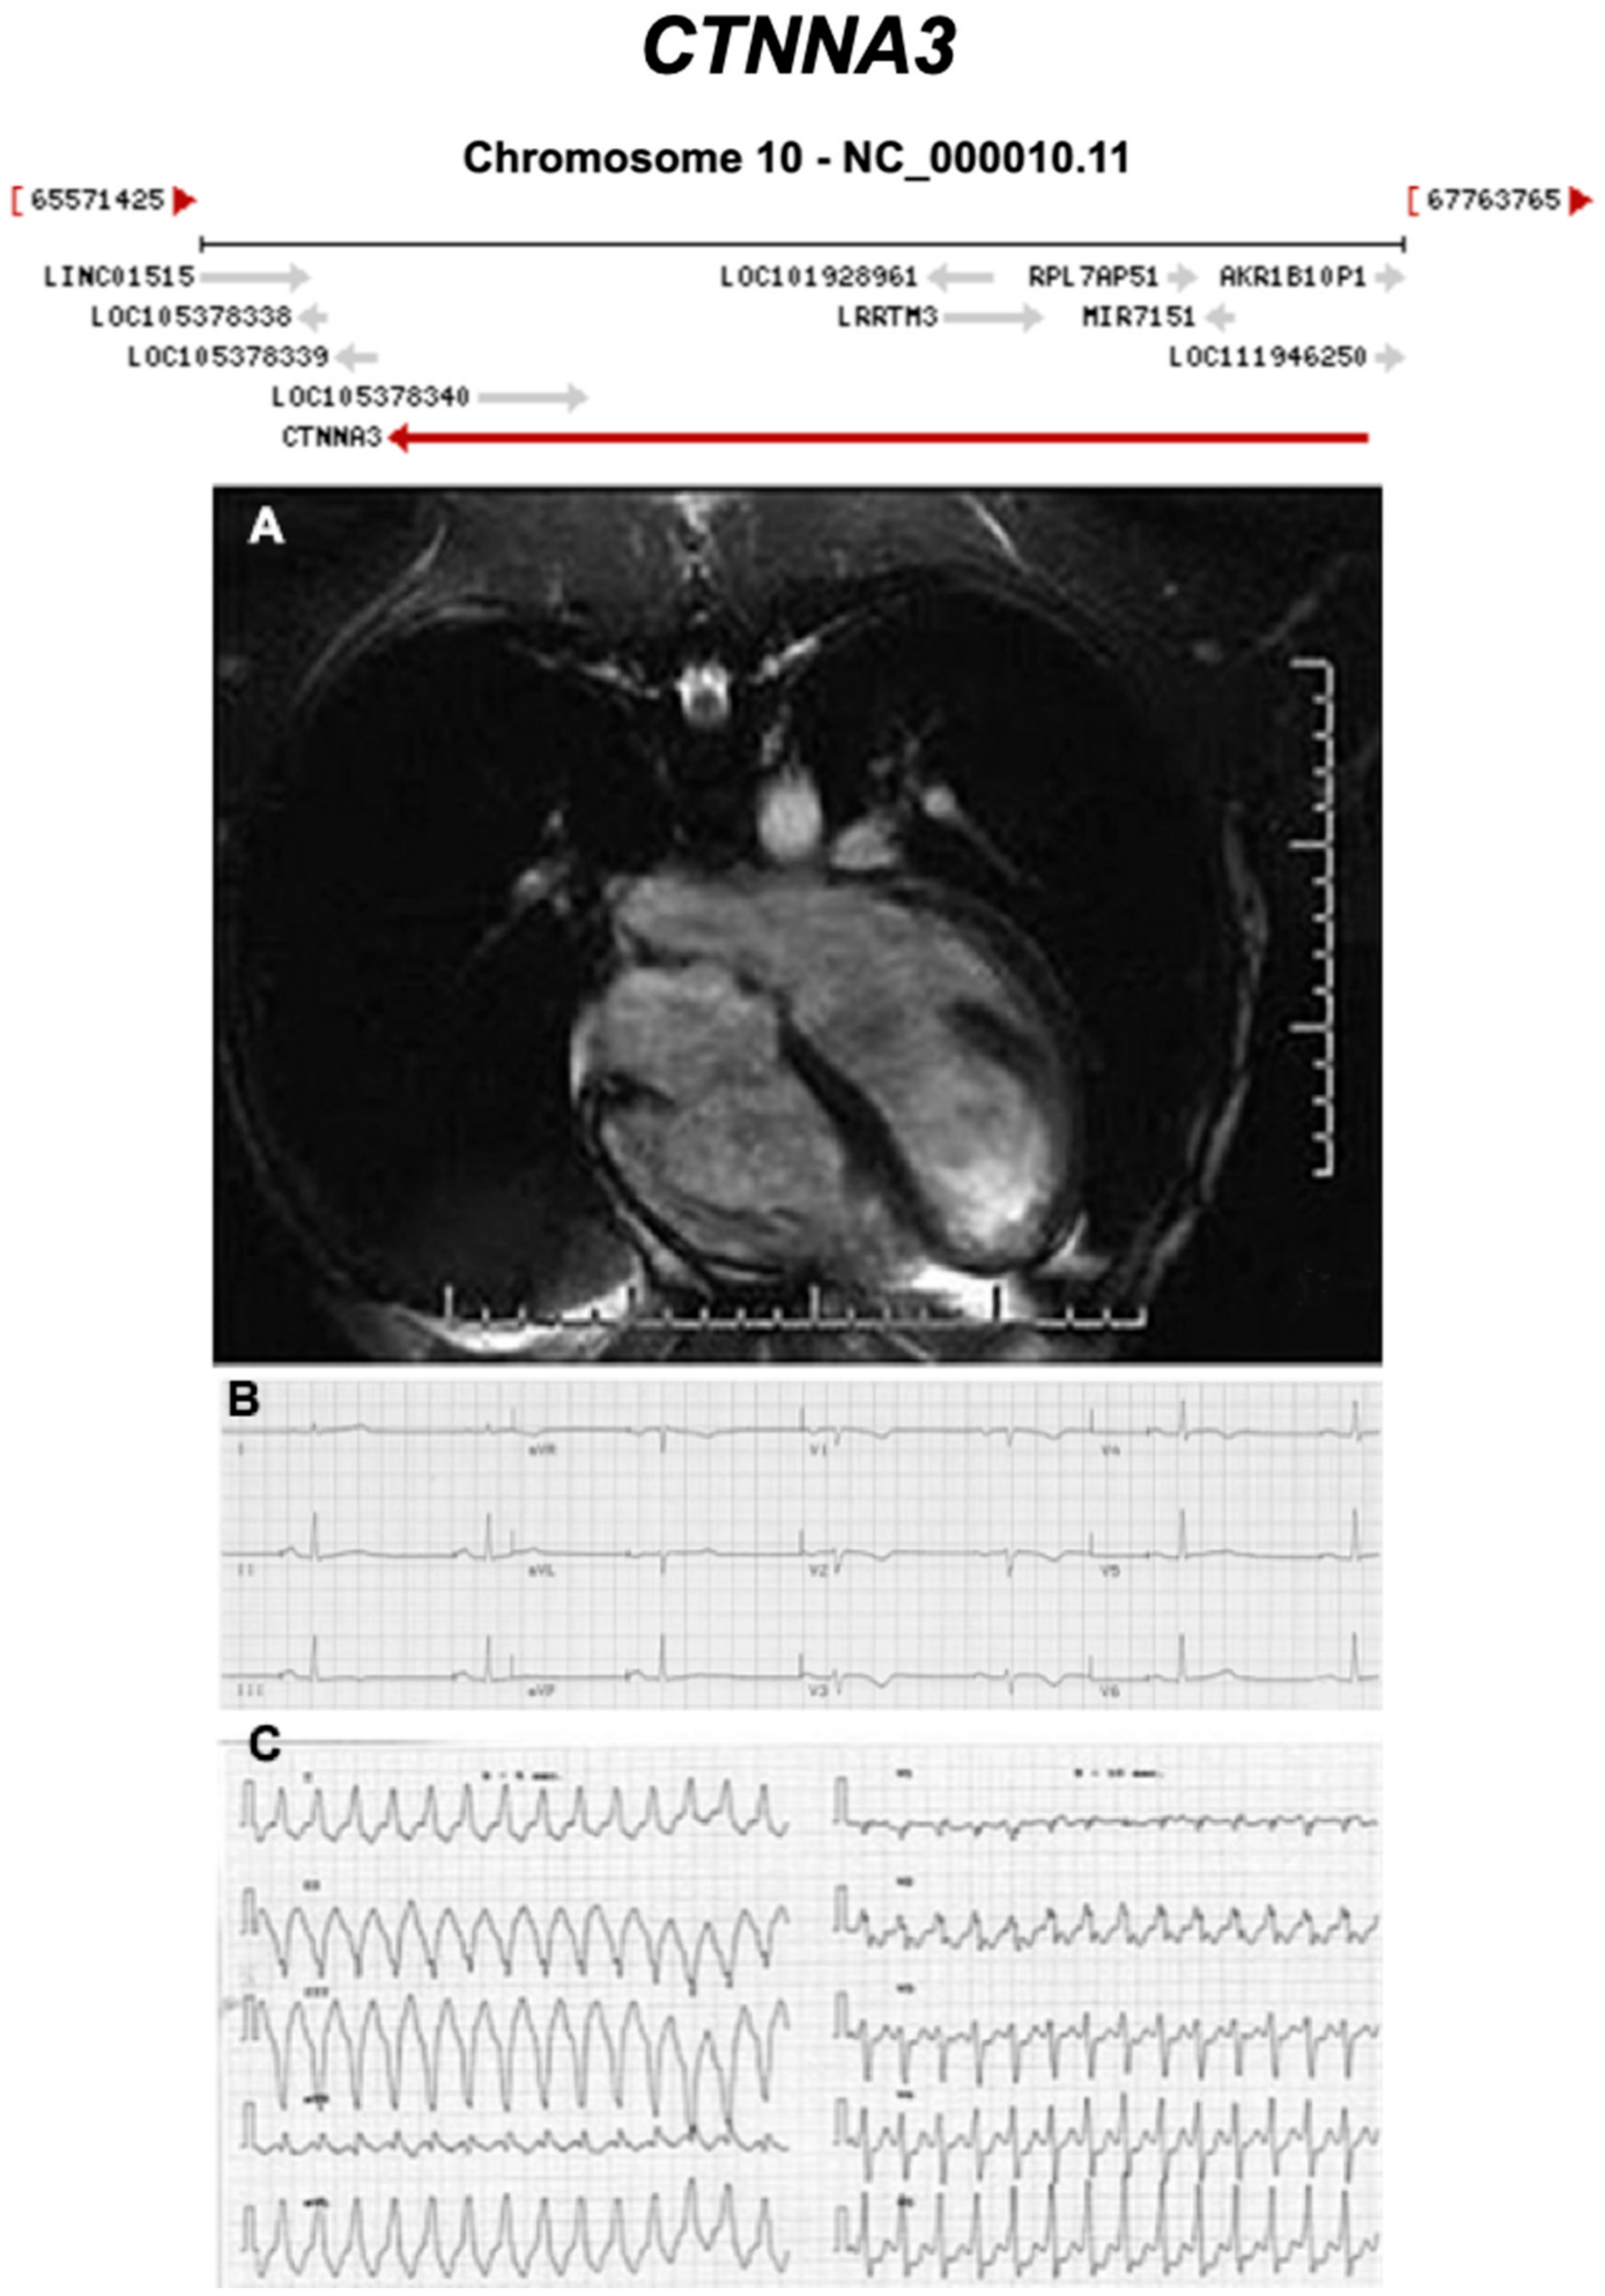

3.2.7. Catenin Alpha 3 (CTNNA3) (Encoded by CTNNA3)

- van Hengel, J.; Calore, M.; Bauce, B.; Dazzo, E.; Mazzotti, E.; De Bortoli, M.; Lorenzon, A.; Li Mura, I.E.A.; Beffagna, G.; Rigato, I.; et al. Mutations in the area composita protein αT-catenin are associated with arrhythmogenic right ventricular cardiomyopathy. Eur. Heart J. 2013, 34, 201–210. [Google Scholar] [CrossRef] [PubMed]

| CTNNA3 | Intercalated Disc | <1% | AD | RV, BIV | ARVC13 | 10q21.3; 27 | Low penetrance | Limited for ARVC |